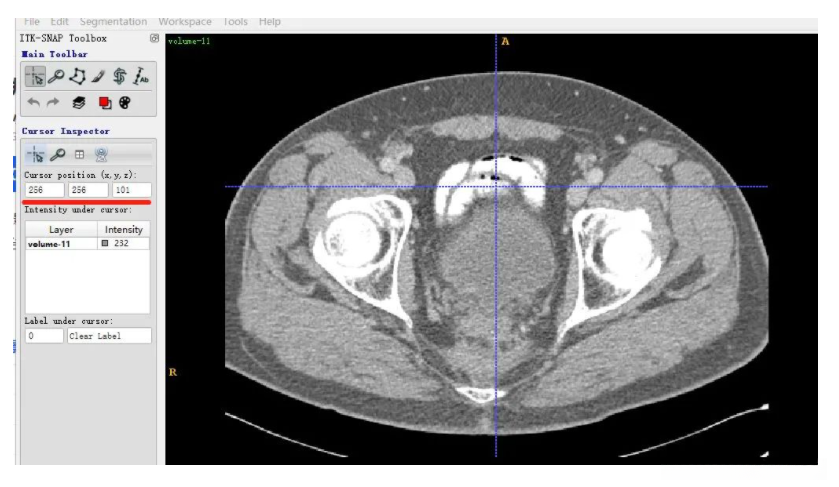

同一个slice在ITK-SNAP可视化结果(注意这里(x,y,z=(256,256,101)),因为itk-snap默认从1开始索引):

可以发现,上下两张x轴一样但y轴方向上下翻转了,这是由于matplotlib显示方式不同,但是不会出现读取数据对不齐的问题。